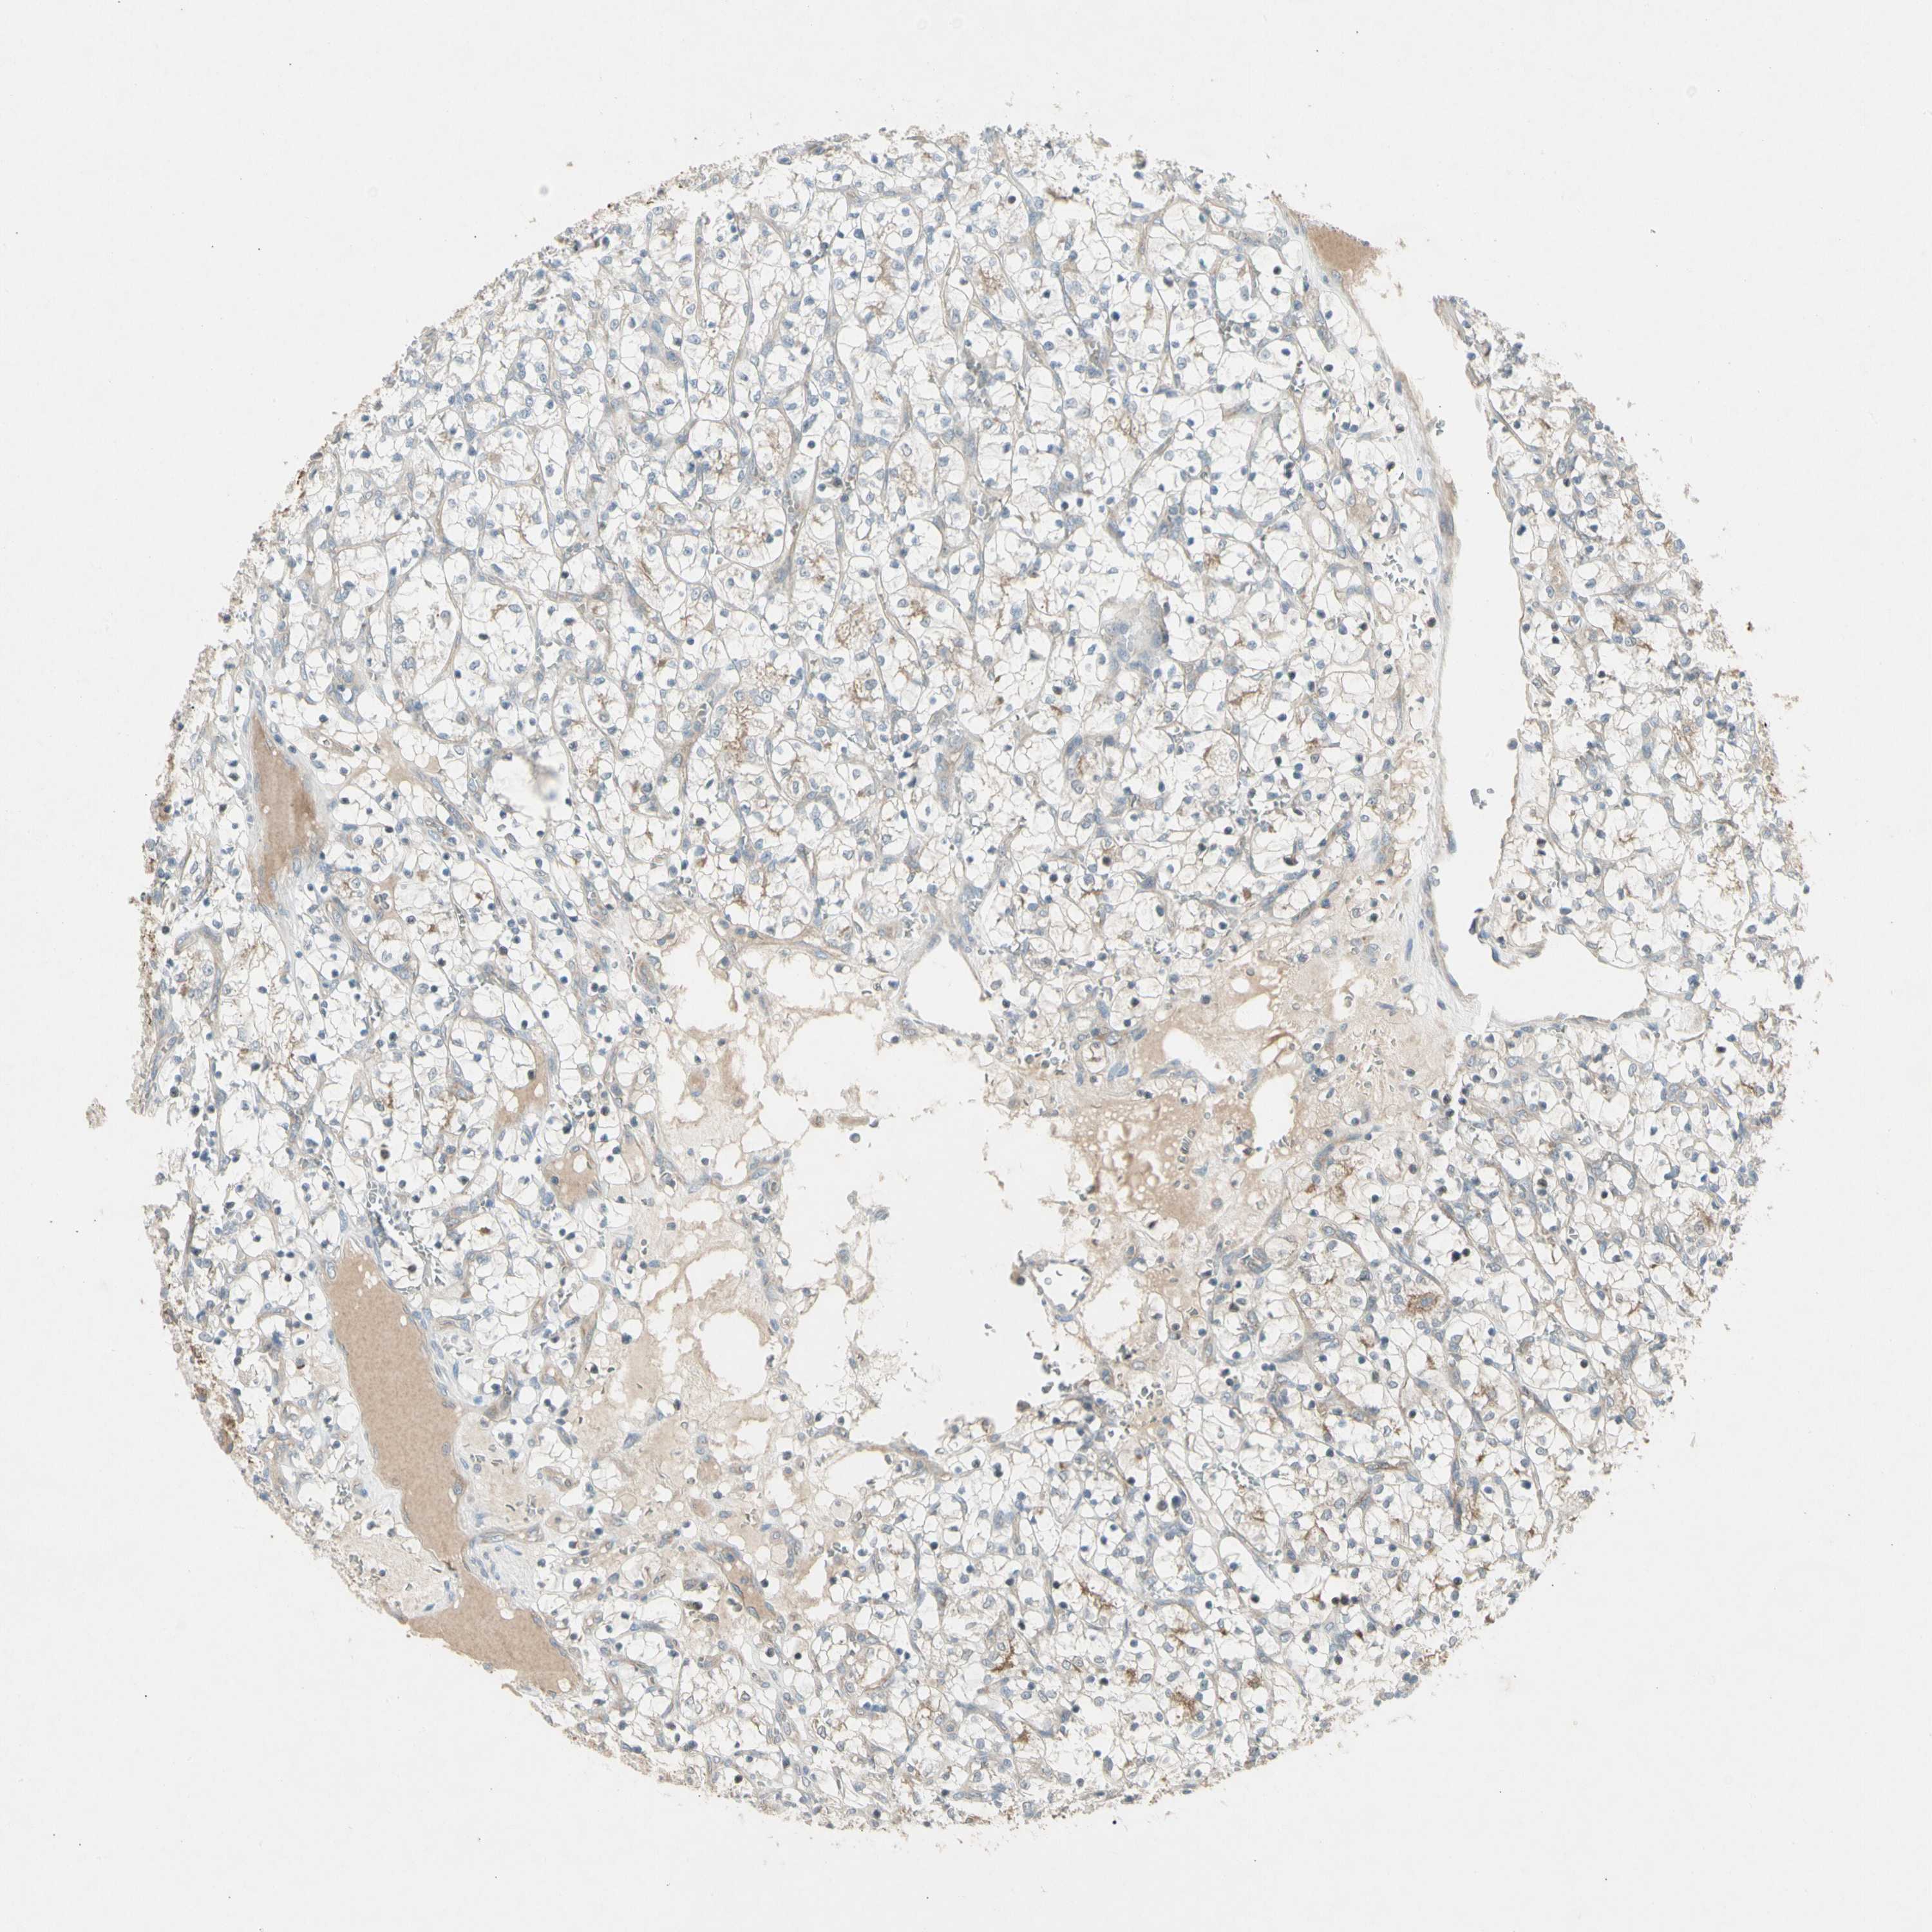

KIDNEY RENAL CLEAR CELL CARCINOMA (VALIDATION) - Interactive survival scatter ploti

The Survival Scatter plot shows the clinical status (i.e. dead or alive) for all individuals in the patient cohort, based on the same data that underlies the corresponding Kaplan-Meier plots. Patients that are alive at last time for follow-up are shown in blue and patients who have died during the study are shown in red.

The x-axis shows the expression levels (FPKM) of the investigated gene in the tumor tissue at the time of diagnosis. The y-axis shows the follow-up time after diagnosis (years). Both axes are complimented with kernel density curves demonstrating the data density over the axes. The top density plot shows the expression levels (FPKM) distribution among dead (red) and alive patients (blue). The right density plot shows the data density of the survived years of dead patients with high and low expression levels respectively, stratified using the cutoff indicated by the vertical dashed line through the Survival Scatter plot. This cutoff is automatically defined based on the FPKM cutoff that minimizes the p-score. The cutoff can be changed by dragging the vertical line or by entering a cutoff value in the square labeled "Current cut-off".

Under the Survival Scatter plot the p-score landscape (black curve; left axis) is shown together with dead median separation (red curve; right axis). Dead median separation is the difference in median mRNA expression between patients who have died with high and low expression, respectively. It is calculated as follows: median FPKM expression of dead patients with high expression - median FPKM expression of dead patients with low expression. This is intended to aid the user in visually exploring custom cutoffs and the associated p-scores and dead median separation.

Individual patient data is displayed and can be filtered by clicking on one or more of the category buttons on the top of the page. Categories describing expression level and patient information include: high, low, alive, dead, female, male and tumor stages. The scale of the x-axis can be toggled between linear and log-scale by clicking on the "x log" button. Mouse-over function shows TCGA ID, patient information and mRNA expression (FPKM) for each patient.

& Survival analysisi

Kaplan-Meier plots summarize results from analysis of correlation between mRNA expression level and patient survival. Patients were divided based on level of expression into one of the two groups "low" (under cut off) or "high" (over cut off). X-axis shows time for survival (years) and y-axis shows the probability of survival, where 1.0 corresponds to 100 percent.

PANK2 is not prognostic in Kidney Renal Clear Cell Carcinoma (validation)

Best expression cut offi

Based on the FPKM value of each gene, patients were classified into two groups and association between prognosis (survival) and gene expression (FPKM) was examined. The best expression cut-off refers the FPKM value that yields maximal difference with regard to survival between the two groups at the lowest log-rank P-value. Best expression cut-off was selected based on survival analysis .

When clicking on this number, the vertical dashed line indicating cut-off, the interactive survival plot, and the Kaplan-Meier curve will be adjusted to show results based on the best expression cut-off.

: 15.34

P scorei

Log-rank P value for Kaplan-Meier plot showing results from analysis of correlation between mRNA expression level and patient survival.

N/A

TCGA RNA samplesi

RNA-seq data is reported as average FPKM (number Fragments Per Kilobase of exon per Million reads), generated by the The Cancer Genome Atlas (TCGA) .

Normal distribution across the dataset is visualized with box plots, shown as median and 25th and 75th percentiles. Points are displayed as outliers if they are above or below 1.5 times the interquartile range. FPKM values of the individual samples are presented next to the box plot.

Average pTPM 14.6

Number of samples 100